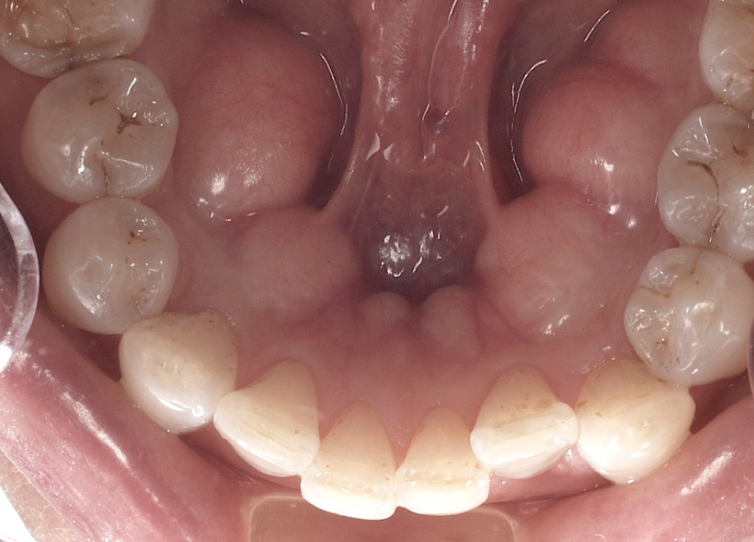

強く噛み合う力を支えるため、歯を支える顎の骨が増殖し隆起します。

歯ぎしりや食いしばりをする際に舌を歯に押し付けるため舌の表面に歯の形に沿った圧痕ができます。